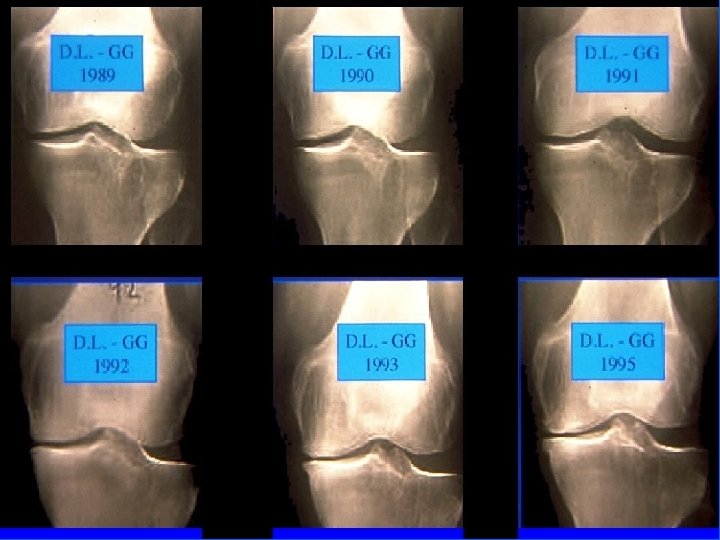

Arthrose fémoro-tibiale Iconographie • Radiographie : – Face en appui bipodal – Profil – Schuss (face en charge à 30° de flexion) pour compartiment post • Signes: – Pincement interligne – Ostéophytose – Ostéosclérose sous-chondrale avec géodes

Arthrose fémoro-tibiale Pronostic • Évolution très variable • Pas de facteurs pronostique bien individualisé mais semble que – obésité – antécédents traumatiques = Facteurs d’évolutivité